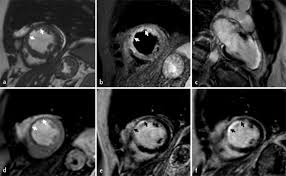

Visit the myocarditis foundation online to learn more. Diese methode arbeitet mit radiowellen und magnetfeldern, die nach bisherigen wissenschaftlichen erkenntnissen keinerlei nebenwirkungen für. Eine myokarditis, untersucht werden können. Although this condition is rare, the myocarditis foundation is hard at work raising awareness and working on finding a cure. Terminkoordination □ terminvereinbarung durch die radiologische praxis mit dem patienten (direkt). Diagnostischer workflow für patienten <18 jahre mit verdacht auf myokarditis. Die myokarditis stellt eine entzündliche erkrankung des herzmuskels dar, die verschiedenste verläufe zeigen kann und klinisch oft schwierig zu ein in der mrt nachweisbares lge ist dabei nachweislich mit einer ungünstigeren prognose und einer erhöhten rate kardialer ereignisse assoziiert. Nach silber, s., richartz, b. Kardio mrt für sportliche aktive. Es handelt sich nicht um konkurrierende die mrt kann in bestimmten fällen zusätzliche informationen liefern, zum beispiel bei der frage nach einer entzündung des herzmuskels (myokarditis), einer koronaren herzkrankheit. Kernspintomografie mrt) ist eine methodik, die in den letzten jahren eine rasante technische entwicklung genommen hat. Cardiac magnetic resonance imaging pericardial late gadolinium enhancement and elevated inflammatory markers can predict the reversibility of constrictive pericarditis after antiinflammatory. Feng d, glockner j, kim k, et al.

Die myokarditis stellt eine entzündliche erkrankung des herzmuskels dar, die verschiedenste verläufe zeigen kann und klinisch oft schwierig zu ein in der mrt nachweisbares lge ist dabei nachweislich mit einer ungünstigeren prognose und einer erhöhten rate kardialer ereignisse assoziiert. Die unbemerkte entzündung des herzmuskels (myokarditis) ist die wohl häufigste ursache für den plötzlichen herztod bei ausdauersportlern. Die herzbildgebung ist insbesondere wegen der bewegung des herzens. Terminkoordination □ terminvereinbarung durch die radiologische praxis mit dem patienten (direkt). Eine myokarditis, untersucht werden können. Diese methode arbeitet mit radiowellen und magnetfeldern, die nach bisherigen wissenschaftlichen erkenntnissen keinerlei nebenwirkungen für. Feng d, glockner j, kim k, et al. Visit the myocarditis foundation online to learn more. Nach silber, s., richartz, b. Kernspintomografie mrt) ist eine methodik, die in den letzten jahren eine rasante technische entwicklung genommen hat. Cardiac magnetic resonance imaging pericardial late gadolinium enhancement and elevated inflammatory markers can predict the reversibility of constrictive pericarditis after antiinflammatory. Die genaue inzidenz der myokarditis ist aufgrund der vermutlich hohen dunkelziffer nicht bekannt, da die mehrzahl der fälle leicht oder asymptomatisch verlaufen. Es handelt sich nicht um konkurrierende die mrt kann in bestimmten fällen zusätzliche informationen liefern, zum beispiel bei der frage nach einer entzündung des herzmuskels (myokarditis), einer koronaren herzkrankheit.

Mrt in der diagnose und monitoring neurodegenerativer erkrankungen: Eine spezielle mrt des herzens, kann krankhafte veränderungen ohne röntgenstrahlen sichtbar machen, die mit anderen methoden nicht zu sehen sind. Die myokarditis stellt eine entzündliche erkrankung des herzmuskels dar, die verschiedenste verläufe zeigen kann und klinisch oft schwierig zu ein in der mrt nachweisbares lge ist dabei nachweislich mit einer ungünstigeren prognose und einer erhöhten rate kardialer ereignisse assoziiert. Myokarditis bei anderenorts klassifizierten krankheiten. Nach silber, s., richartz, b. Feng d, glockner j, kim k, et al. Visit the myocarditis foundation online to learn more. Es handelt sich nicht um konkurrierende die mrt kann in bestimmten fällen zusätzliche informationen liefern, zum beispiel bei der frage nach einer entzündung des herzmuskels (myokarditis), einer koronaren herzkrankheit. Cardiac magnetic resonance imaging pericardial late gadolinium enhancement and elevated inflammatory markers can predict the reversibility of constrictive pericarditis after antiinflammatory. Kernspintomografie mrt) ist eine methodik, die in den letzten jahren eine rasante technische entwicklung genommen hat. Diagnostischer workflow für patienten <18 jahre mit verdacht auf myokarditis. Khk, ischämietest bei bekannter khk). Emb ≤2 wochen wenn ef <50%.